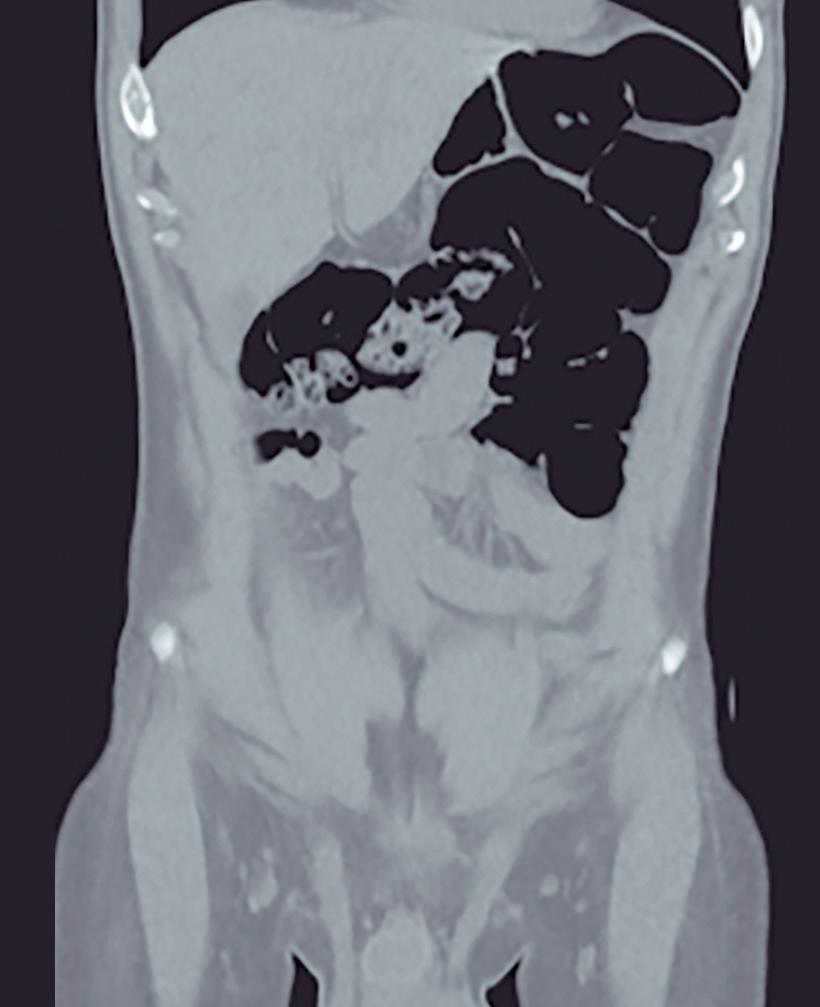

CASOS CLÍNICOS Coexistencia de cáncer de colon y malrotación intestinal: un raro desafío anatómico y oncológico

Nicolás Lavorato, Alejandro Moreira Grecco, Tomás Flores, Rodrigo Morales, Gonzalo Hugo Zapata, Luis Ernesto

Sarotto

Nicolás Lavorato, Alejandro Moreira Grecco, Tomás Flores, Rodrigo Morales, Gonzalo Hugo Zapata, Luis Ernesto Sarotto